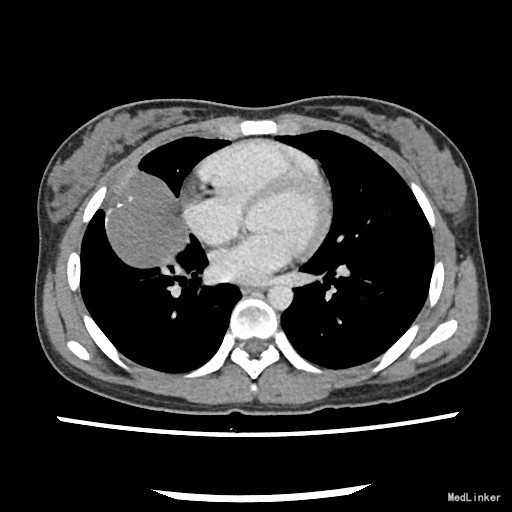

患者:女,18岁 主诉:体检发现右肺结节1月 病史:者1月前体检发现右肺结节1月,不伴咳嗽、胸闷气促、呼吸困难、胸痛、咯血,当时患者因高考未能及时治疗。近期体重无明显改变。

查体:一般情况良好,心肺腹均未见异常。 胸部X片示:右肺结节,性质待定,建议进一步检查。

诊断:肺部肿物(查因?) 治疗:住院后完善相关检查,胸部螺旋CT提示:右肺中叶囊实性肿物,恶性肿瘤待排。排除手术禁忌症,遂于全麻下行胸腔镜辅助下右中下肺叶切除,淋巴结清扫术。术后病理示:粘液表皮样癌。 (右中叶开口肿物)纤维结缔组织内见较多表皮样细胞、粘液细胞及中间细胞,部分形成腺腔样结构,结合免疫组化及特殊染色,符合粘液表皮样癌。 免疫组化结果(②):CEA(+),CK14(灶性+),TTF-1(-),Vimentin(-),CK7(+),Ki-67(2%+),CK5/6(+),P63(+)。 特殊染色结果:PAS(+),d-PAS(+),粘液(+)。